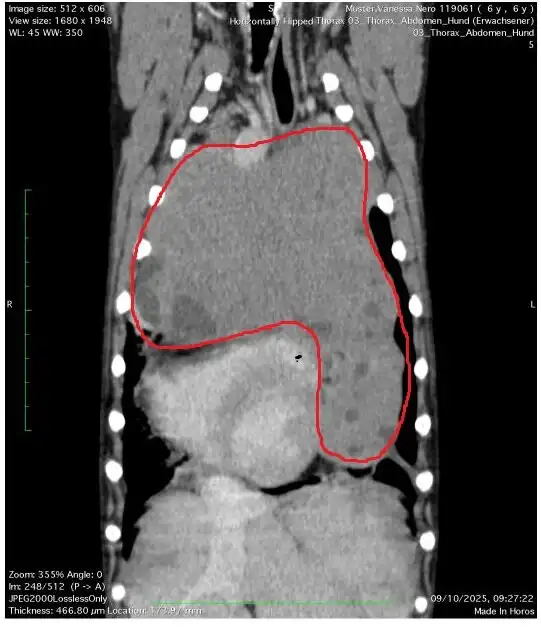

Jetzt steht er vor seiner größten Herausforderung: Ein sehr großer Tumor muss dringend operativ entfernt werden.

Der Tumor ist so groß, dass er bereits einen Großteil von Neros Lunge verdrängt hat. Ihm stehen nur noch ca. 20 % seiner Lungenkapazität zur Verfügung.

Dank seines unglaublichen Überlebenswillens konnte sich Nero an diese Einschränkung anpassen. Er ist ein Kämpfer und trotz seiner Atemnot rennt er noch über die Wiesen und spielt begeistert mit seinem Lieblingsstofftier. Aber die Zeit drängt.